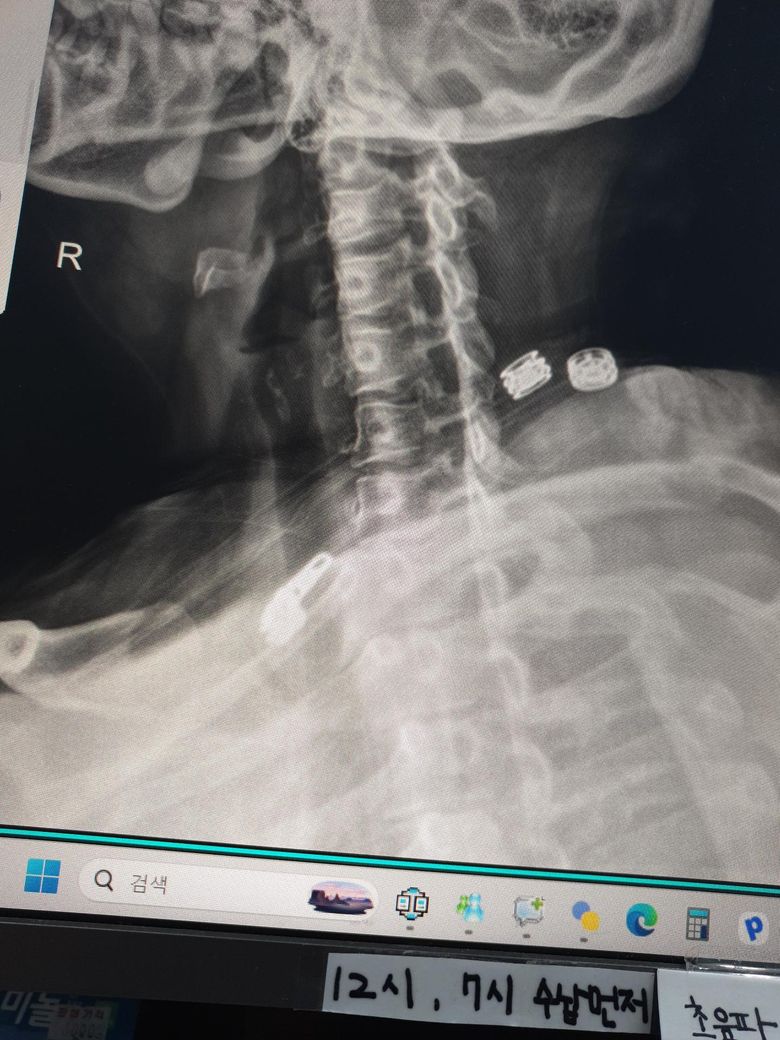

지금 현재 목 상때입니다 지금 오른쪽 목 신경이 시작하는 부분이 많이 아프고(후두동맥 부분) 신경이 뻣치는 느낌이 있어요 가만히 있어도 통증이 있습니다 지금 베개는 안맞는건지 불편해서 깨거나 신경시 뻣치는 느낌이 나서 깨요 가격대는 4만원까지 생각하고 있고 등이랑 어깨가 말려있어서 높이 않으면 숨이 막혀요 옆으로 누워서 자구요

• 1번 째 사진